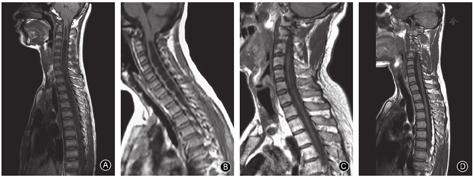

小脑扁桃体下疝程度可分为三级:Ⅰ级(疝体下缘超过枕大孔下方5 mm,但未到C1后弓上缘),Ⅱ级(疝体下缘位于C1后弓水平),Ⅲ级(疝体下缘至C1后弓下缘)。

脊髓空洞的形态分为四种类型,即膨胀型、念珠型、细长型和局限型(图2)[23]。

计算最大S/C比值时,应在同一节段测量脊髓空洞前后径和脊髓直径[24]。

脊髓空洞的长度定义为脊髓空洞跨越的椎体数。